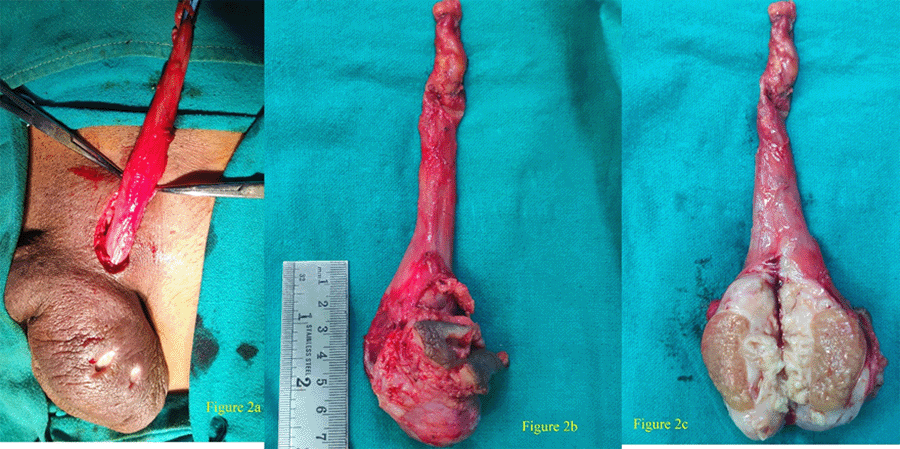

A scrotal wound culture demonstrated Staphylococcus aureus and was negative for AFB. The patient was admitted, kept on intravenous antibiotics, and planned for orchidectomy. The testis was delivered through a left inguinal approach with high-up orchidectomy and wide excision of the ulcer (Figure 2B). Intraoperatively, the testis and the epididymis were enlarged to around 7 × 4 cm, hard and communicating ulcer could be appreciated from the testes to the scrotal skin. The cut surface showed a well-circumscribed but ill-defined lesion, which was firm and pale with areas of necrosis and grayish-white color changes (Figure 2C).

Figure 2. Intraoperative Photo of Scrotum. Published With Permission

A) Enlarged and minimally tender left testes with firm-to-hard consistency, erythematous, edematous, and indurated left scrotal area with ulcer around 1 × 0.5 cm with yellowish foul-smelling discharge. Left inguinal incision can be appreciated along with spermatic cord being delivered with high inguinal approach. B) Enlarged testis and epididymis mass around 7 × 4 cm—hard and communicating ulcer could be appreciated from lump to scrotal skin. C) Well-circumscribed but ill-defined lesion, firm and pale, with areas of necrosis and grayish-white color changes along epididymis and some part of testis.